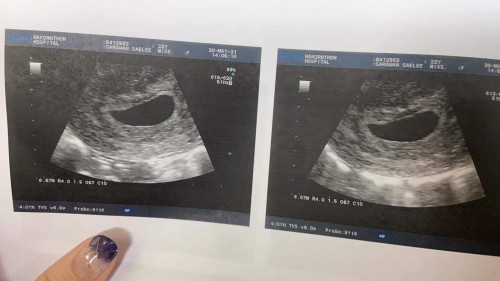

หมอบอกว่าเราท้องลม 90%ใครเคยมีประสบการณ์แบบนี้ไหมค่ะ อีก2อาทิตย์หมอนัดอัลตราซาวด์อีกรอบ

เคยท้องลมค่ะ ถ้าแม่ๆ ยังไม่มีเลือดออก ก้อถือว่ายังไม่ต้องกังวลมาก ถ้าอยากแน่ใจไปตรวจเลือดดูค่าฮอร์โมน HCH ดูค่ะ อันนี้จะให้ผลแม่นยำว่าท้องลมรึป่าว